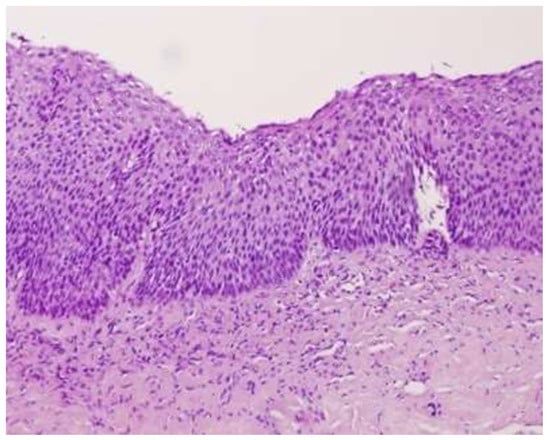

- Darragh, T.M.; Colgan, T.J.; Cox, J.T.; Heller, D.S.; Henry, M.R.; Luff, R.D.; McCalmont, T.; Nayar, R.; Palefsky, J.M.; Stoler, M.H.; et al. The Lower Anogenital Squamous Terminology Standardization Project for HPV-Associated Lesions. Int. J. Gynecol. Pathol. 2013, 32, 76–115. [Google Scholar] [CrossRef]